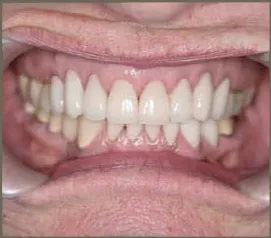

The patient had worn teeth and uneven gingival tissue. Laser recontouring of gingival tissue and then 20 ceramic crowns were fabricated.

Front teeth were veneered to address the wear and unevenness of the smile.

The patient had heavy wear from acid reflux. We whitened her teeth and had ten ceramic crowns fabricated to correct wear and angulation of her teeth. The patient was very pleased with the results!

This patients teeth position was corrected with Invisalign. The gingival tissue was recontoured with a soft tissue laser. Then, the front six teeth were restored with all ceramic crowns.